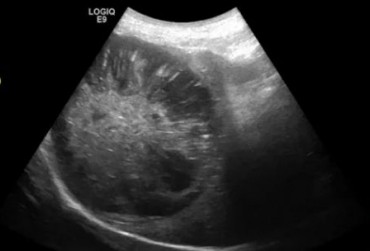

Kot europ. 12l. Stary zawał nerki.

24 czerwca 2019

Wojciech Atamaniuk

Czytaj więcej